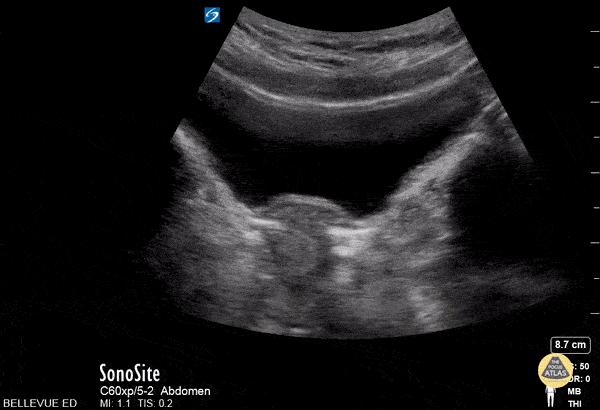

OB/Gyn - Transabdominal Uterus Transverse

This is a clip of the uterus in transverse view using the transabdominal approach. The large anechoic structure in the center is the bladder in transverse view, and immediately deep to the bladder is the round uterine fundus. As the probe fans through the uterus we see some dark shadowing within it, likely due to artifact created by an IUD. The fallopian tubes are also faintly visible bilaterally branching off the uterus.